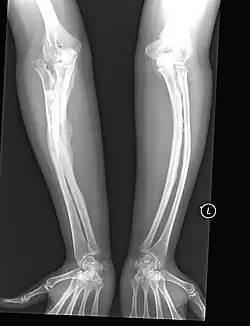

Left forearm

Spine, chest, and pelvis

Right forearm

Right femur

Four X-rays of a 24-year-old American man (Fredrick Brennan), who had had more than one hundred bone fractures in his lifetime, and received a childhood clinical diagnosis of type IV–B OI. Genetic diagnosis in 2018 identified a previously uncatalogued pathogenic variant in the gene which encodes proα2(I) chains of type I procollagen, COL1A2, at exon 19, substitution c.974G>A. Due to childhood neglect and poverty, Brennan never received surgery to implant intramedullary rods. Malunions are evident as the humerus and femur were broken in adolescence, but orthopedic care did not follow. Severe scoliosis, as well as kyphosis, are also evident. The unavoidably low contrast in the film is due to a combination of Brennan's obesity and low bone mineral density (BMD). His BMD Z-score was -4.1 according to results of a dual-energy X-ray absorptiometry (DXA) scan also done in 2018.